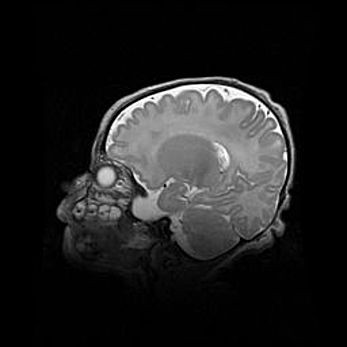

Аномалия Денди-Уокера. Признаки гипоплазии мозолистого тела.

Возраст: 5 месяцев 3 дня

Вес: 5550 г

Пол: мужской

Окружность головы: 39 см

Срок гестации: 40 недель

Аномалия Денди-Уокера – это порок развития головного мозга, для которого характерна триада симптомов: гипотрофия или аплазия червя мозжечка и/или полушарий мозжечка, расширение четвёртого желудочка с формированием ликворной кисты задней черепной ямки, гипертензионная гидроцефалия различной степени.

Гипоплазия мозолистого тела относится к дефектам внутриутробного этапа развития мозговой ткани, возникающим в процессе закладки структур головного мозга, что происходит на начальных этапах развития эмбриона.